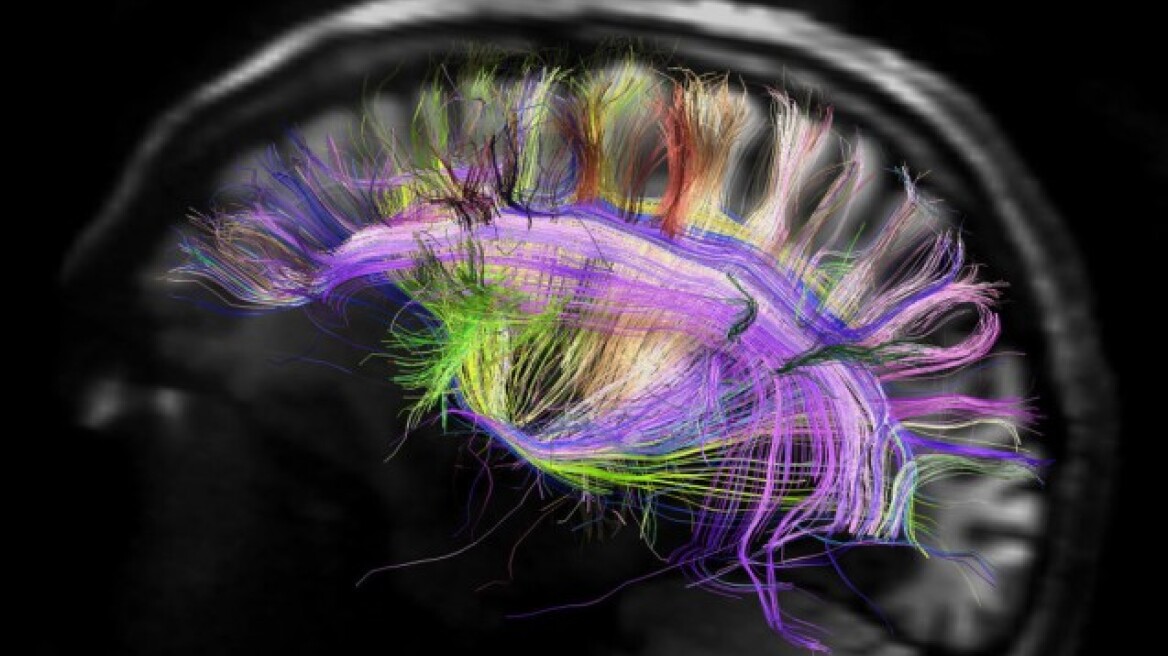

Οι νευρώνες του εγκεφάλου αλληλεπιδρούν στέλνοντας ο ένας στον άλλον χημικά μηνύματα, και γι’ αυτό ονομάζονται νευροδιαβιβαστές. Το Γάμμα-Αμινοβουτυρικό οξύ (GABA) είναι ο πιο κοινός ανασταλτικός νευροδιαβιβαστής, ο οποίος είναι σημαντικός για τη συγκράτηση της νευρικής δραστηριότητας, αποτρέποντας τους νευρώνες από το υπερδιεγερθούν σε άσχετα ερεθίσματα. Ερευνητές, με επικεφαλή τον Δρ. Tobias Bast, από τη Σχολή Ψυχολογίας του Πανεπιστημίου του Nottingham έχουν διαπιστώσει ότι ελαττωματική ανασταλτική νευροδιαβίβαση και ασυνήθιστα αυξημένη δραστηριότητα στον ιππόκαμπο μειώνει την μνήμη και την προσοχή μας.

Ο ιππόκαμπος είναι ένα μέρος του εγκεφάλου που βρίσκεται μέσα στους κροταφικούς μας λοβούς και παίζει σημαντικό ρόλο στην καθημερινή μας μνήμη, για απλά γεγονότα, όπως το πού και πότε θα συμβεί κάτι, που παρκάραμε το αυτοκίνητο μας και ούτω καθεξής.

Η έρευνα δείχνει ότι η έλλειψη συγκράτησης στη νευρική πυροδότηση εντός του ιππόκαμπου διαταράσσει το σημείο του, όπου εξαρτάται η μνήμη. Επιπλέον, μπορεί να διαταραχθεί και η προσοχή. Ο Δρ. Bast, δήλωσε: «Η έρευνά μας διεξάγεται σε αρουραίους και υπογραμμίζει τη σημασία της αναστολής της ενεργοποίησης GABA εντός του ιππόκαμπου για την απόδοση της μνήμης και για την προσοχή». Το εύρημα ότι η ελαττωματική αναστολή διαταράσσει τη μνήμη υποδηλώνει ότι η μνήμη εξαρτάται από την ισορροπημένη νευρωνική δραστηριότητα εντός του ιππόκαμπου.

Αυτό είναι ένα σημαντικό εύρημα επειδή παραδοσιακά, οι διαταραχές μνήμης έχουν κυρίως συσχετιστεί με μειωμένη δράση ή βλάβες του ιππόκαμπου. «Δεύτερο σημαντικό εύρημα μας είναι ότι η ελαττωματική αναστολή οδηγεί σε αυξημένη νευρωνική δραστηριότητα εντός του ιππόκαμπου που διαταράσσει την προσοχή, μια γνωστική λειτουργία που συνήθως δεν απαιτείται από τον ιππόκαμπο, αλλά εξαρτάται από τον προμετωπιαίο φλοιό. Αυτό πιθανότατα αντικατοπτρίζει το γεγονός ότι υπάρχουν πολύ ισχυρές νευρωνικές συνδέσεις μεταξύ ιππόκαμπου και προμετωπιαίου φλοιού.